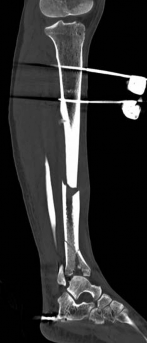

Pre-operative planning is the cornerstone of successful execution in complex pilon-variant tibial shaft fractures. The surgeon must transition from a conceptual understanding of the injury to a concrete, step-by-step surgical blueprint. This begins with high-quality orthogonal radiographs of the entire tibia, ankle, and knee. However, plain films drastically underestimate the degree of articular comminution and central impaction. A fine-cut computed tomography (CT) scan with 2D multiplanar reformats (coronal and sagittal) and 3D surface rendering is absolutely mandatory.

The CT scan allows the surgeon to map the fracture lines, identify the primary articular fragments (Chaput, Volkmann, medial malleolus), and quantify the degree of central die-punch impaction. In an AO/OTA 43C3.3 fracture, where no articular fragment is in continuity with the diaphysis, the surgeon must plan the sequence of reduction. Typically, the fibula is addressed first to restore lateral column length and rotation, provided the fibular fracture is not located at the level of the syndesmosis where fixation might interfere with the lateral surgical approach to the tibia.

Initial management in these high-velocity scenarios mandates the application of a spanning external fixator to achieve skeletal traction, restore length, and allow the soft tissue envelope to recover. This temporary stabilization minimizes ongoing secondary soft tissue trauma from mobile fracture fragments. However, the application of external fixators is not without risk; meticulous pin placement is required. For instance, calcaneal transfixion pins must be placed with strict attention to the neurovascular bundle to avoid iatrogenic tibial nerve irritation, an issue that required revision in the early phase of our index patient's care.